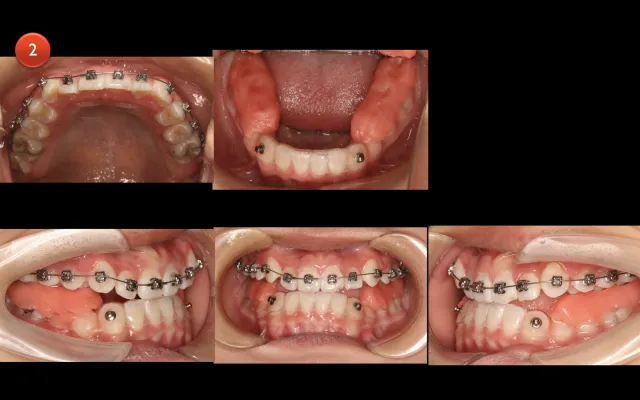

各类错颌畸形,从诊断分析到治疗策略。

各类矫正案例,揭露牙齿移动的底层逻辑。

各类二矫案例,教会学员如何跳坑、避坑。